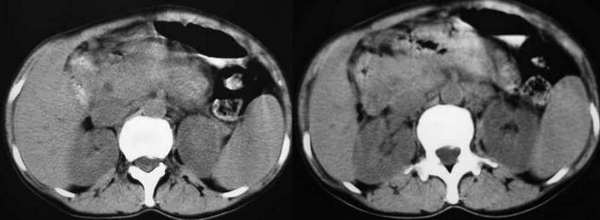

以下是引用东北在2006-1-20 15:36:00的发言:[br]图象少 外生性肝癌并肝内转移侵犯胃窦[br]胰腺的图象少

以下是引用wangqj1976在2006-1-20 21:11:00的发言:[br]不支持胰腺癌的诊断[br]1位置抬高,病变在腹腔干之上, 2胆管、胆囊主胰管不扩张,化验胆红素不高。[br]不支持肝癌[br]1无乙肝、肝硬化病史2病变强化方式[br]支持胃癌可能性大,合并肝转移、胰腺受累。(病人还贫血)[br]脾大,可以用肿瘤压迫脾静脉来解释。[br]建议做上消化道钡餐检查。